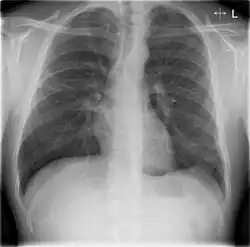

Chest X-rays and X-ray computed tomography (CT) can reveal areas of opacity (seen as white), indicating consolidation.[14] CAP does not always appear on x-rays, sometimes because the disease is in its initial stages or involves a part of the lung not clearly visible on x-ray. In some cases, chest CT can reveal pneumonia not seen on x-rays. However, congestive heart failure or other types of lung damage can mimic CAP on x-ray.[16]

When signs of pneumonia are discovered during evaluation, chest X-rays and examination of the blood and sputum for infectious microorganisms may be done to support a diagnosis of CAP. The diagnostic tools employed will depend on the severity of illness, local practices and concern about complications of the infection. All patients with CAP should have their blood oxygen monitored with pulse oximetry. In some cases, arterial blood gas analysis may be required to determine the amount of oxygen in the blood. A complete blood count (CBC) may reveal extra white blood cells, indicating infection.